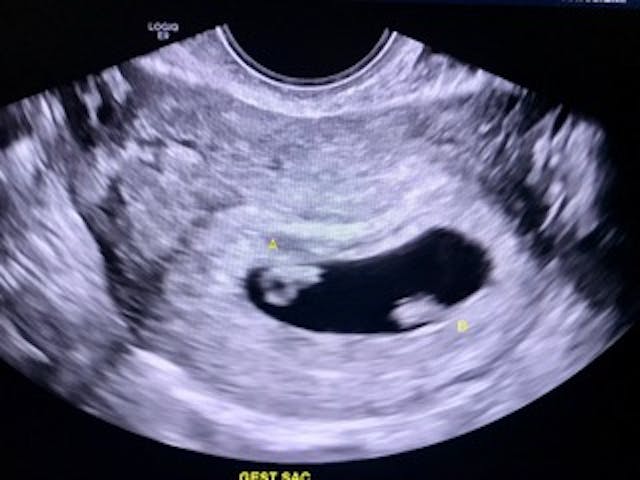

I made it to six weeks and five days in that pregnancy, until one night I was shocked to discover bright red blood everywhere — more than I had ever seen in my life. I was terrified and heartbroken. I knew I must be having a miscarriage, and we drove to the ER in a panic. After a few hours of waiting, I was elated and overwhelmed when an ultrasound technician turned her screen towards me and showed me TWO perfect babies. Twins! Little heads; little nubs for arms and legs. Fluttering heartbeats — the most beautiful sight and sound.

I now cherish that memory and the precious ultrasound photo of my babies from the only time I saw them both alive. A little over a month later, at the end of my first trimester, I found myself back at the same ER, all alone and bleeding profusely. My worst fears were realized in the doctor’s calloused words: “So, the ultrasound only shows one baby….”